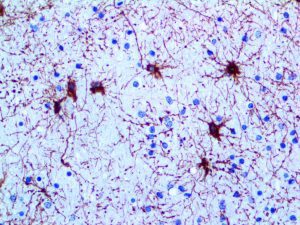

It is the ICU physician who is most likely to witness one of the deadliest manifestations of the abnormal immunological response, the cytokine storm syndrome (CSS). This response is also referred to by some as the cytokine release syndrome (CRS). CSS is characterized by continuous activation and expansion of macrophage and lymphocyte populations, which secrete large amounts of cytokines, causing the cytokine storm. This massive cytokine release is akin to hemophagocytic lymphohistiocytosis (HLH) disease, a syndrome characterized by initial unchecked and persistent activation of cytotoxic T lymphocytes and NK cells.